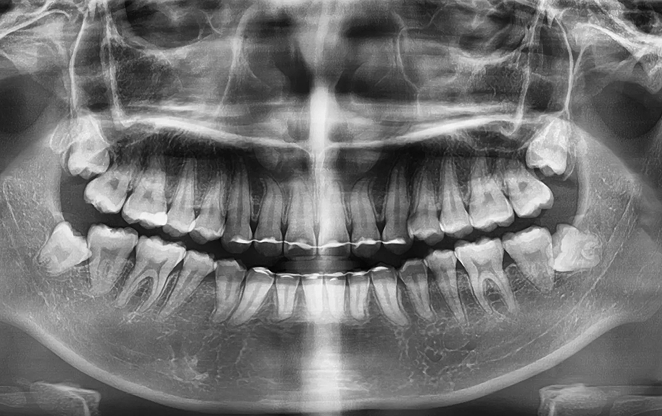

초등학생 1차 교정은 영구치가 나오기 전 혼합치열기에 시작하는

교정입니다. 이 중요한 시기에 치아가 제대로 자리 잡을 수 있도록,

아이의 밝은 미래를 위한 준비를 도와드릴게요.